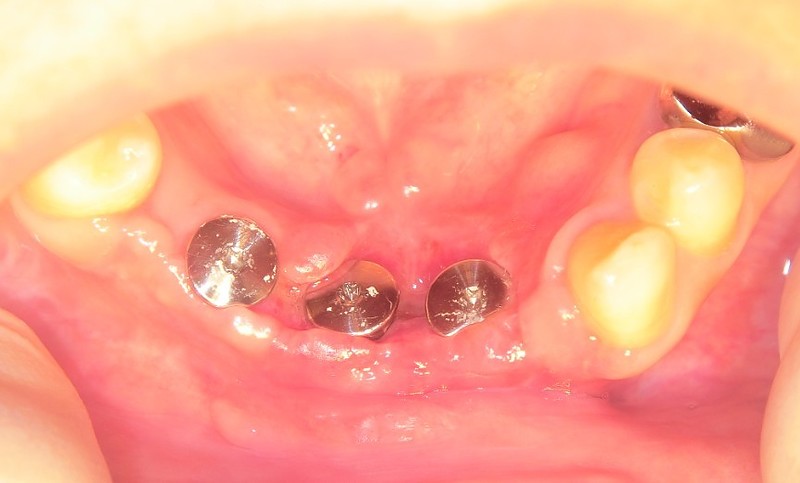

【症例:交通事故で前歯を失った方のケース】

インプラントを土台にし、歯としての機能を再建した治療例です。